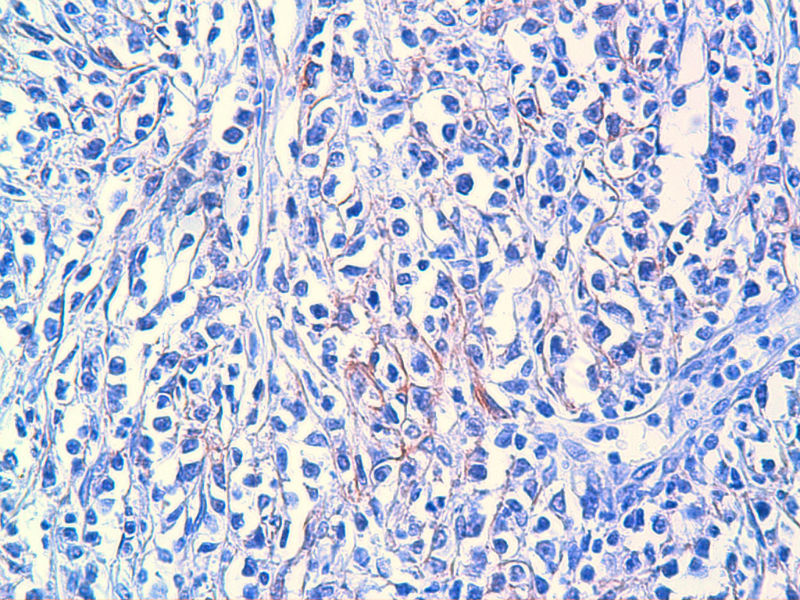

免疫组化染色:CA125(-),PLAP(-),NSE灶状阳性,Vimentin(+),a-inhibin(-),CK7(-),CK20(-),CD15(-),PSA(-),S100(-),MyoD1(-),CD38(-),CD56(-),HMB45(-),CK8(-),NF(-),CGA(-),syn(+),MPO散在(+)可能是炎细胞吧,LCA(+),CD133(+).

今天又做了免疫组化,请大家帮看看。CD10(-),CD138(-),CDX2(-),CD3(-),CyclinD1(-),CD2(-),CD117(-),CD7(-),CD30(-),CD23(-);CD20强(+),BCL-2,Bcl-6,EMA,PAX-5,MUM-1,CD5,ALK,CD68都是散在阳性,大家帮确定一下是否阳性。B细胞淋巴瘤可以确定了,不知是哪种类型的?